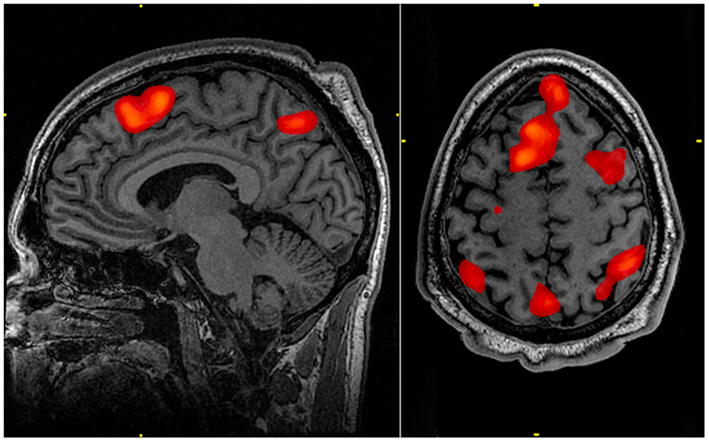

Este proceso se denomina hiperactivación (más) o hipoactivación (menos). La hiperactivación puede detectarse en los escáneres de IRMf cuando las zonas del cerebro se resaltan en rojo y la hipoactivación se indica con zonas azules.

A continuación, la RMNf traza un mapa de las zonas activadas mediante vóxeles (al crear una imagen tridimensional del cerebro, una unidad de vóxel representa una porción diminuta de tejido cerebral en la imagen), produciendo imágenes neuronales.

Las zonas resaltadas son partes activas del cerebro.

Por ejemplo, ciertas zonas del cerebro aparecerán cuando una persona esté trabajando en una tarea de memoria.

Resonancia Magnética Funcional fMRI escáner memoria de trabajo StudySmarterFig. 2: Un escáner fMRI durante tareas de memoria de trabajo revela zonas activas del cerebro.